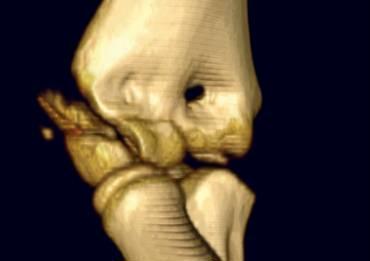

Gãy lồi cầu ngoài (4).

Vì hầu hết các cấu trúc liên quan đều là sụn, nên rất khó xác định chính xác mức độ của gãy xương.

Đôi khi đường gãy chạy qua phần đã cốt hóa của chỏm con. Trong những trường hợp đó, việc chẩn đoán khá dễ dàng.

Trường hợp bên trái cho thấy gãy lồi cầu ngoài kéo dài qua phần đã cốt hóa của chỏm con.

Đây là gãy loại Milch I. Khớp khuỷu vẫn còn vững.

Vì di lệch quá nhiều nên cần phải tiến hành kết hợp xương.